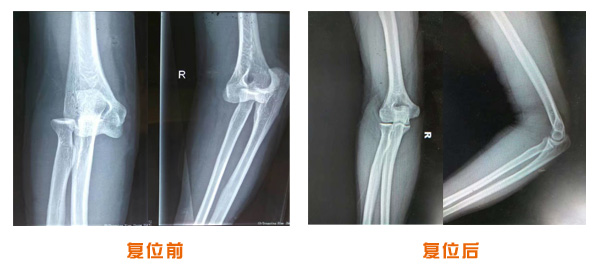

肥城市安駕莊梁氏骨科醫(yī)院是一所以梁氏手法正骨配合膏藥為特色的現代化??漆t(yī)院。

梁氏骨科術始創(chuàng)于清雍正年間,歷經八代,至今已有三百年歷史。據1929年泰安縣志載“梁瑞圖先生,字增生,號蓮峰,安駕莊人,精岐黃并發(fā)明接骨,凡跌打車凡跌打車軋皮不破而碎骨者......【詳細】 |